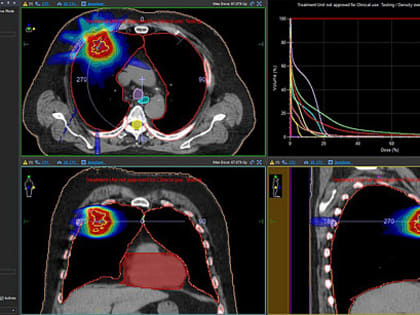

В Кирове внедрили инновационный метод лечения онкологии

Современные методы лечения включают прием лекарств, операции, лучевую терапию.